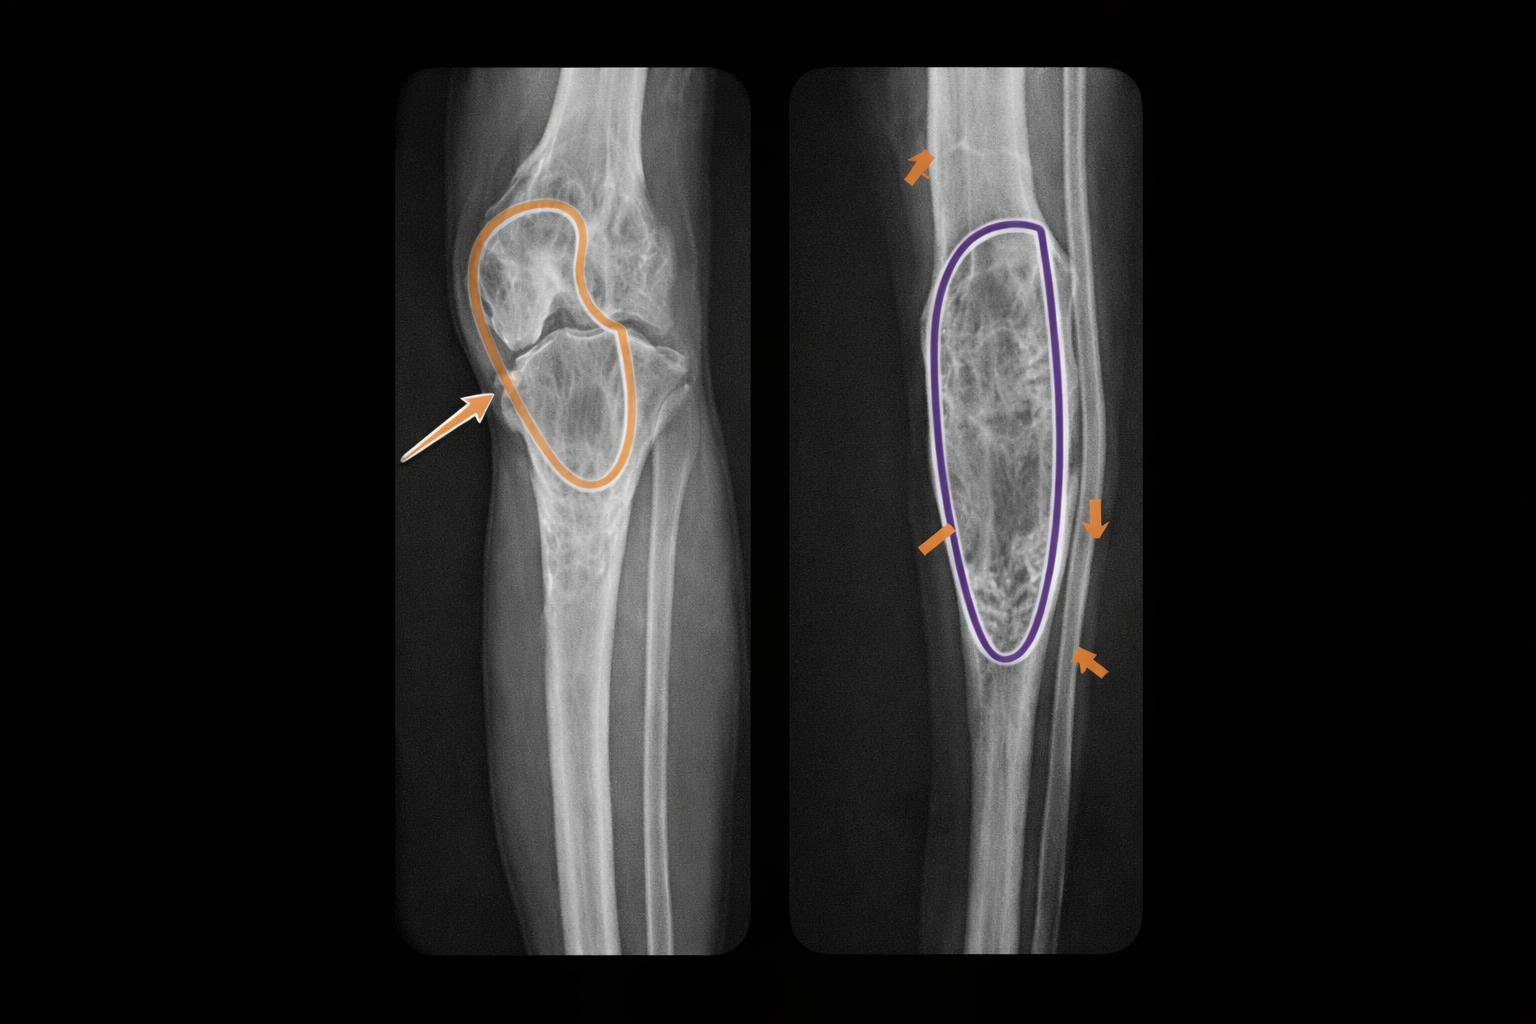

🦴 Displasia osteofibrosa (OFD): lesión cortical tibial infantil, con diferencial crítico con adamantinoma

La displasia osteofibrosa (OFD), también descrita como lesión de Kempson-Campanacci, es una lesión fibro-ósea rara que afecta sobre todo a niños pequeños. Su “firma” es su localización en la cortical anterior de la tibia, con posible arqueamiento anterior. Lo más importante en la práctica es no confundirla con un adamantinoma (más agresivo y de mayor edad), y evitar tratamientos innecesarios en casos típicos.

Hallazgo radiológico característico

Radiografía (RX)

- 🩻 Lesión radiolúcida, cortical anterior, con márgenes lobulados y esclerosis.

- 🩻 Lesiones grandes pueden erosionar cortical e invadir cavidad medular.

- 🩻 En tibia suele no ocupar todo el diámetro; en peroné puede ser más “circunferencial”.

- 🩻 Raramente múltiples focos a lo largo de la diáfisis (ojo: puede simular adamantinoma).